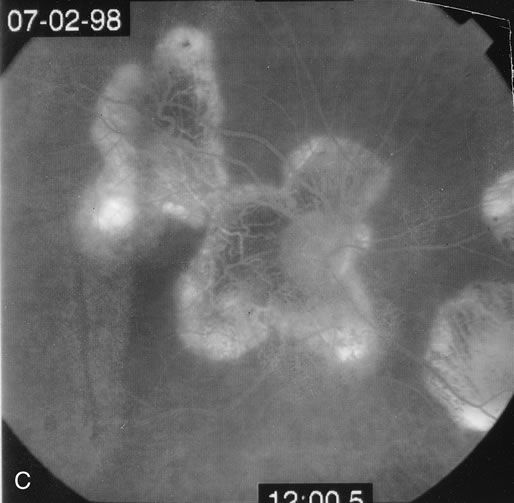

Some patients present with subretinal bands that extend between chorioretinal scars. In addition there may be initial active yellow choroidal lesions that subsequently become atrophic. Vitreous cells are usually present although they may be few and difficult to detect. Visual acuity loss in these cases may be due to active choroidal neovascularization, subretinal bands under the fovea, or from cystoid macular edema. The vast majority of affected patients are women with a mean age of 27 years and both eyes are usually involved. The affected individuals tend to be myopic.49 The age range is from 6 years to 76 years and there is no racial predilection.40 Whether it is a separate disease or a more severe form of multifocal choroiditis is controversial (Figs. 10 and 11). Aggressive therapy is warranted because it has a poorer prognosis than most cases of multifocal choroiditis. This syndrome has been called either diffuse subretinal fibrosis or progressive subretinal fibrosis syndrome.

Fig. 10. A. Fundus photograph showing the subretinal fibrosis extending from the disc to the periphery in a case of diffuse subretinal fibrosis. B. Fundus photograph showing the marked fibrosis in the midperiphery. C. Multifocal choroiditis type lesions noted in the inferior retina.

Fig. 11. A. Subretinal fibrosis in a case of multifocal choroiditis. B. Fellow eye showing classic coalescent hyperpigmented chorioretinal scars of multifocal choroiditis. These scars also can be seen in presumed histoplasmosis syndrome, but the subretinal fibrosis is extremely rare in presumed ocular histoplasmosis syndrome (POHS).